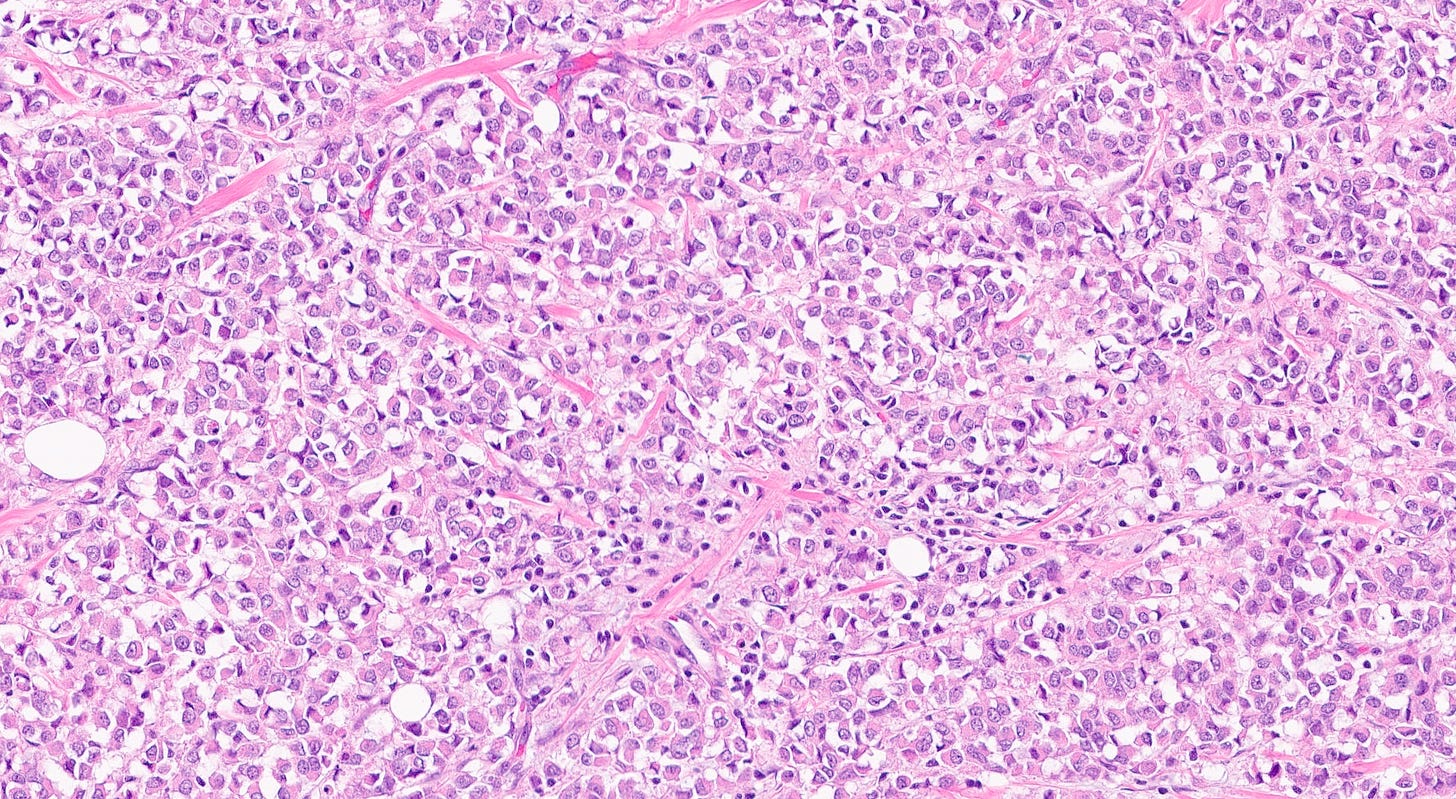

Pleomorphic lobular carcinoma

Pleomorphic lobular carcinoma is a less common subtype of infiltrating lobular carcinoma (15%) with cellular dyscohesion and histologic architecture similar to classic infiltrating lobular carcinoma plus pleomorphic cytologic features similar to those seen in pleomorphic LCIS or high grade DCIS. Its molecular profile and immunostaining pattern (including the loss of E-cadherin) support a common origin with infiltrating lobular carcinoma with the acquisition of further molecular alterations.

It typically occurs in postmenopausal women ages 60 - 80 and is more commonly represented in BRCA2 carriers, in whom it presents at a much younger age.

Most patients present with a poorly defined palpable breast mass. Patients typically have a more advanced stage (large tumors and axillary lymph node metastasis) than patients with invasive ductal carcinoma (IDC). The cancer is more frequently multifocal or multicentric.

Treatment consists of surgical resection (conservative for local disease, mastectomy if multifocal) and adjuvant therapy (usually endocrine therapy, possibly anti-HER2 therapy if appropriate.

Its prognosis is similar to that of other high grade breast carcinomas of similar stage or grade, although some studies suggest its histology is associated with poorer survival.

Pleomorphic lobular carcinoma - microscopic images

The precursors of pleomorphic lobular carcinoma are pleomorphic lobular carcinoma in situ and classic LCIS, which frequently coexist. They were discussed previously.